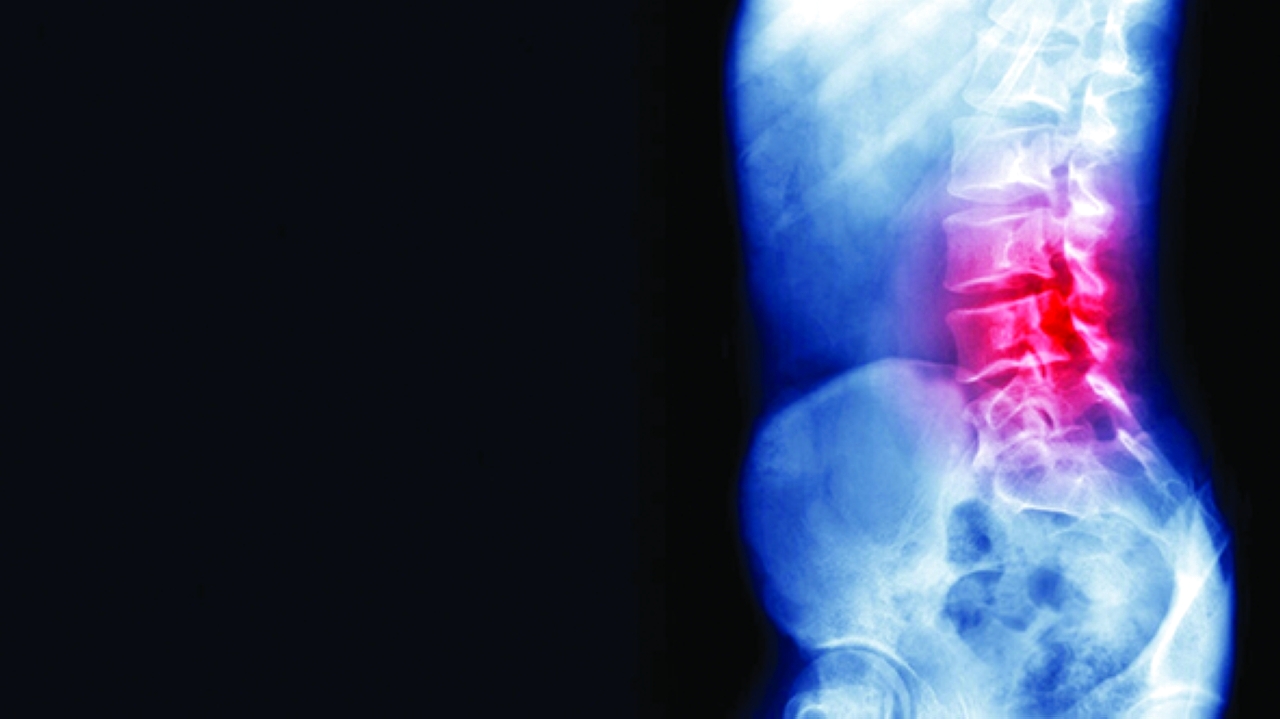

كشفت صور سينية مروعة كيف ألحق غاز الضحك الضرر بالعمود الفقري لرجل، ما جعله غير قادر على المشي، وفقاً لصحيفة «ذي صن». وذهب الرجل (32 عاماً)، إلى قسم الطوارئ بعد أن تعرض لـ«وخز في ذراعيه وساقيه» لمدة ستة أسابيع. وقبل شهرين من الواقعة، بدأ الرجل في استنشاق أكسيد النيتروز، المعروف باسم غاز الضحك، يومياً.

وكشف الفحوصات إن الحبل الشوكي بدأت تظهر عليه علامات اعتلال النخاع، نتيجة نقص فيتامين B12، الذي يتسبب به أكسيد النيتروز.